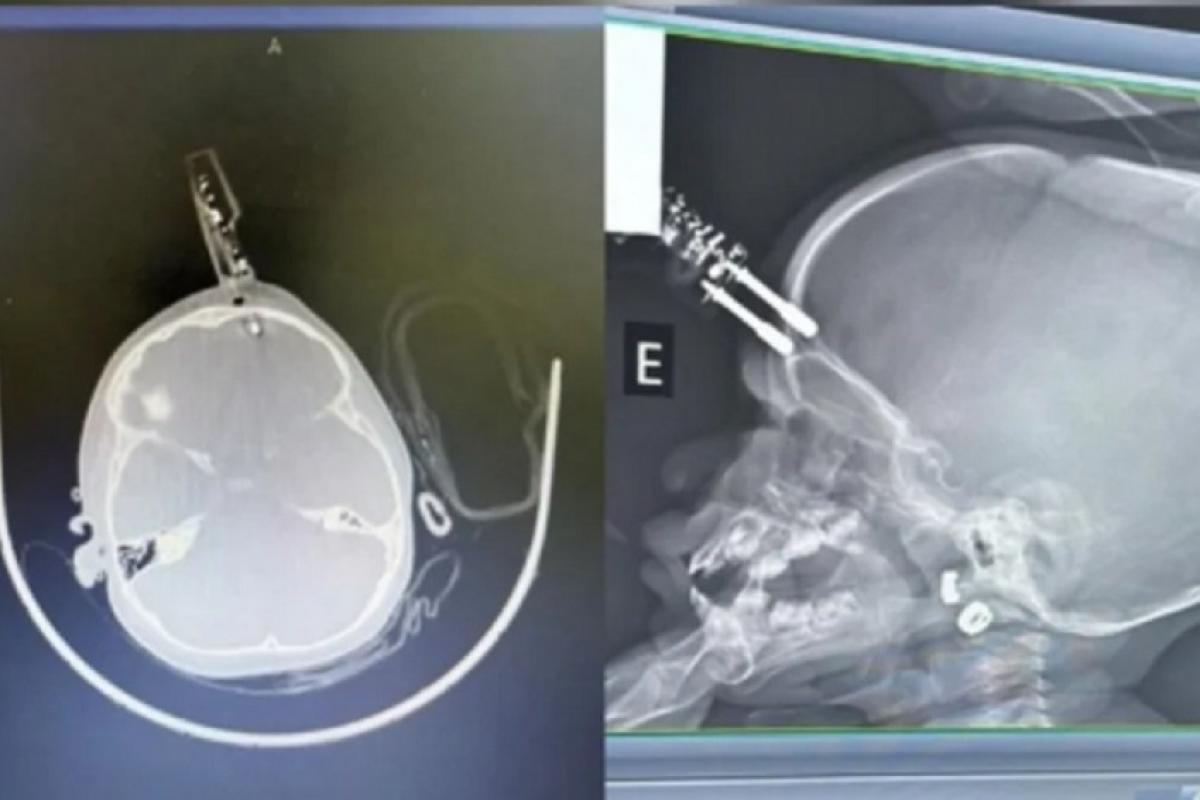

Uma menina de 1 ano precisou passar por uma cirurgia de urgência após sofrer um grave acidente doméstico, na terça-feira (13). A criança caiu da cama e teve um carregador cravado na testa. Apesar da gravidade, ela segue internada em observação e não apresenta, até o momento, sinais de sequelas neurológicas.

Imagens do atendimento mostram que o carregador perfurou o crânio na região frontal, próximo ao olho. Informações preliminares apontam que a mãe da criança havia ido ao banheiro quando o acidente aconteceu.

A menina foi encaminhada ao hospital e levada diretamente ao centro cirúrgico. No local, passou por procedimento para retirada do objeto e reconstrução da área atingida.